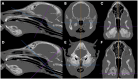

Craniomandibular osteopathy (CMO) is a proliferative, self-limiting, non-neoplastic disease of growing dogs characterised by excessive new bone formation on the skull and mandible. The radiographic findings of CMO are well described; however, limited reports of the computed tomographic (CT) appearance are available. This paper aims to characterise the spectrum of CT findings that can occur with CMO. The study is retrospective, descriptive, multicenter, and includes 20 cases. Age at presentation ranged from 6 weeks to 12 months, with no sex predisposition. Scottish terriers were overrepresented (65%); other breeds included Cairn terrier, Jack Russell terrier, Staffordshire bull terrier, labrador retriever, golden retriever, akita and Slovakian rough-haired pointer (one of each breed). Terrier breeds represented 80% (16/20) of the patient cohort. Mandibular osteoproliferation was present in all patients (marked in 80%, bilateral in 95%), affecting the rostral mandible in 25%, body in 85%, and ramus in 80%. Tympanic bulla osteoproliferation was present in 60% (12/20) of patients (all marked, bilateral in 75%). Cranial osteoproliferation (frontal, parietal, temporal, occipital bones or maxilla, or combinations of them) was present in 90% (18/20) of patients (40% marked, 27% moderate, 33% mild). Nasopharyngeal narrowing was seen in all 12 patients with tympanic bulla osteoproliferation (67% marked, 27% moderate) and caused nearly complete occlusion in two of them. External ear canal stenosis was seen in 55% (11/20) of patients (63% marked, 37% moderate, all bilateral). Temporomandibular joint (TMJ) impingement was suspected in 83% (10/12) of patients with marked tympanic bulla osteoproliferation (75% bilateral). Osteolysis with a moth-eaten pattern was seen in the mandible of 10/20 dogs, the calvarium of 5/20 dogs, and the maxilla of 1/20 dogs (5%). Lymphadenomegaly (mandibular and medial retropharyngeal) was found in 15/20 patients (70% mild, 30% moderate). The most severe CT changes were seen in Scottish terriers. CT allows for detailed characterisation of the bony changes associated with CMO, including the effects occurring secondary to osteoproliferation surrounding the tympanic bullae such as TMJ impingement, external ear canal stenosis, and nasopharyngeal narrowing. Osteoproliferation affecting the cranium and the presence of osteolysis were seen more frequently in this study than previously reported in CMO.